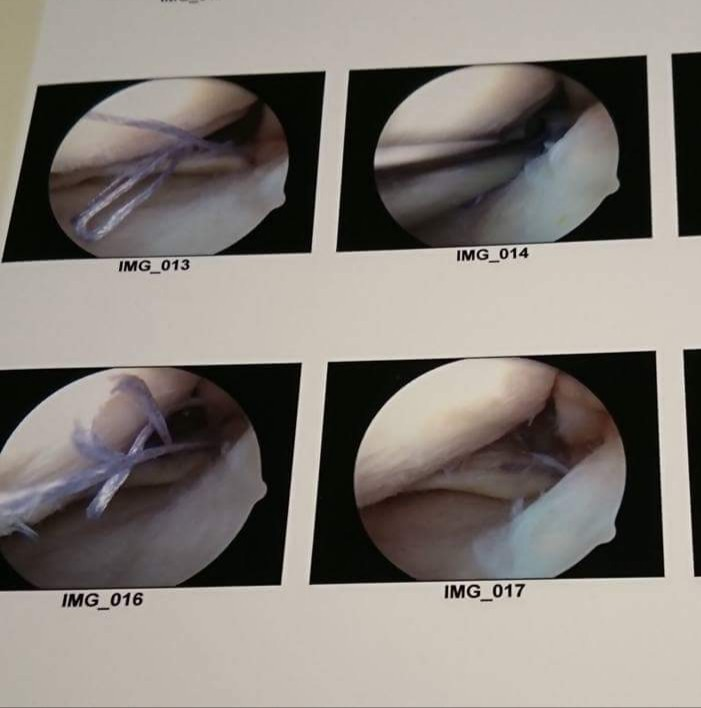

2年程前から左膝を痛め、1年間富山の病院で治療して頂いてましたが、今後の事を考え、今年の4月に半月板縫合手術を受けました。

内視鏡手術だし、ちょちょっと手術して10日程入院すれば元通り‼なんて気軽に思っていましたが、半月板の縫合手術は簡単なものではなく術後の回復も考えていたように早くはありませんでした。